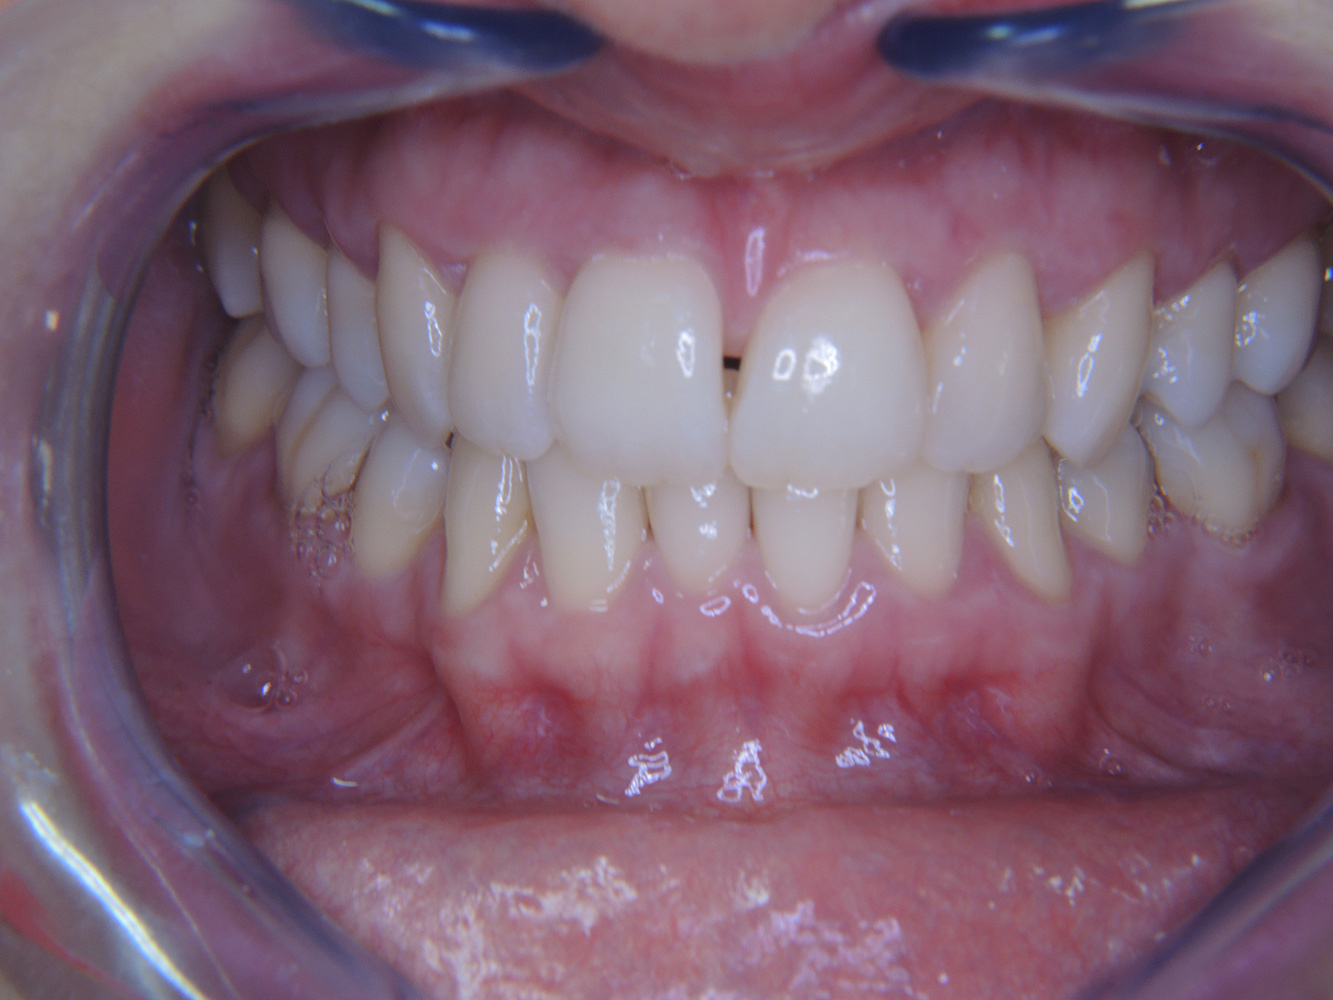

Die mundgesunde Diabetikerin

Eine 51-jährige mundgesunde Diabetikerin stellt sich zur Präventionssitzung vor. Die Blutzuckerwerte sind stabil bei einem HbA1c = 6,2%, folglich gilt sie mit dem entsprechenden Medikament Metformin (Antidiabetikum) als suffizient eingestellt. Die Patientin hat keine bestehenden Versorgungen oder orale Vorerkrankungen. Anhand der aktuellen Befunde lässt sich eine Gingivitis bei sonst stabilem parodontalem Zustand (Stage II, Grad B) feststellen. mehr Infos